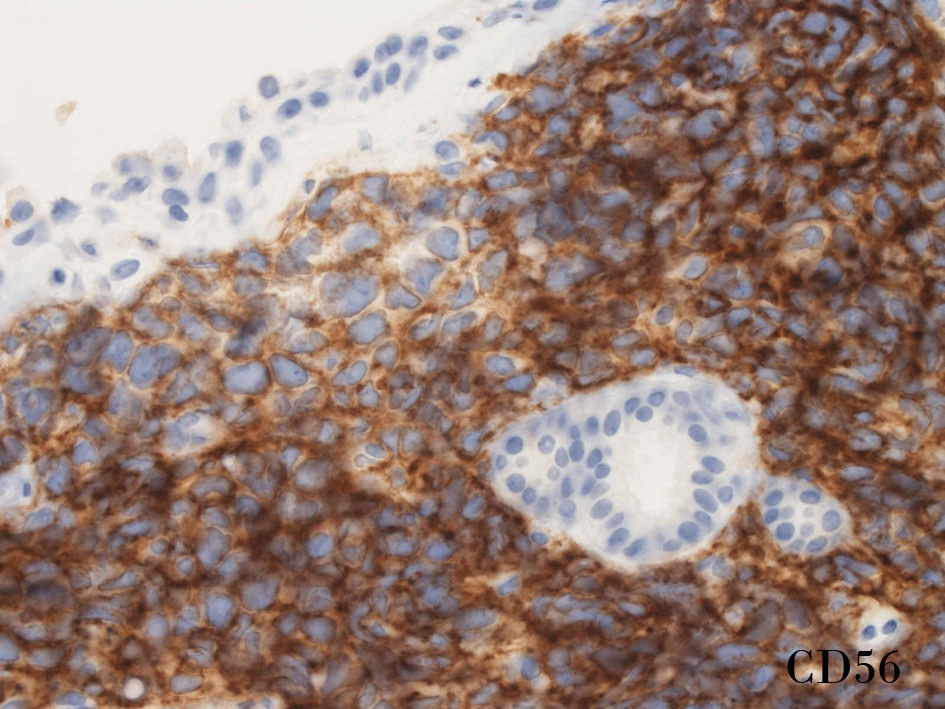

免疫染色

CD56.jpg

CD56rha.jpg

CD56CD56S-100

small round cell tumorの中でrhabdomyosarcomaは腫瘍細胞に種々の抗原が陽性となるため診断を誤ることがあり注意が必要である*1

*1 Bahrami A, et al., Aberrant expression of epithelial and neuroendocrine markers in alveolar rhabdomyosarcoma: a potentially serious diagnostic pitfall. Mod Pathol. 2008 Jul;21(7):795-806. Epub 2008 May 16. PMID:1848799199